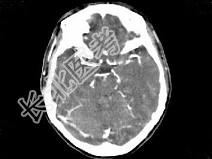

- 单项选择题女,37岁, 产后10天,出现剧烈头痛头昏伴神志不清2天, 根据所提供图像,最可能的诊断是 ( )

A、右侧蛛网膜下腔出血

B、右侧脑膜脑炎

C、右侧硬膜下血肿

D、右侧脑梗死

E、右侧静脉窦血栓形成